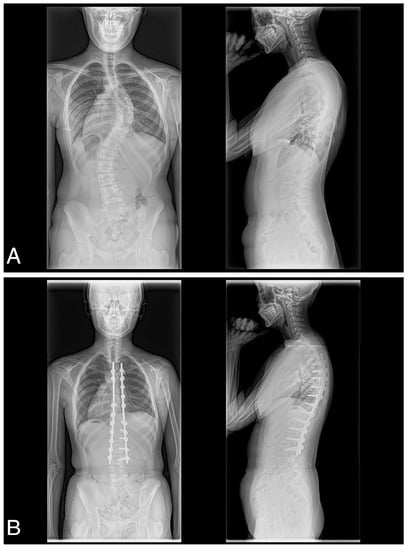

A consecutive series of 41 female patients with AIS with Lenke type 1A (n = 18), 1B (n = 7), 1C (n = 7), 2A (n = 3), 3C (n = 4), 4C (n = 1), or 6C (n = 1) participated in the present study (Table 1). All patients underwent posterior spinal correction and fusion using the 4D anatomical spinal reconstruction technique to correct AIS (Figure 1) []. Patients with syndromic, neuromuscular, or congenital scoliosis were excluded. In addition, because the 4D anatomical spinal reconstruction technique was developed to create postoperative anatomical thoracic kyphosis, we have excluded Lenke 5C main thoracolumbar/lumbar AIS curves. All patients were included in the follow up of the study. All patients in this study gave written, informed consent before participating, and the Institutional Review Board of the authors’ associated institutions authorized the study.

Figure 1.

(A) Preoperative posteroanterior and lateral and (B) postoperative posteroanterior and lateral radiographs obtained of a 17-year-old female with Lenke type 1C scoliosis.